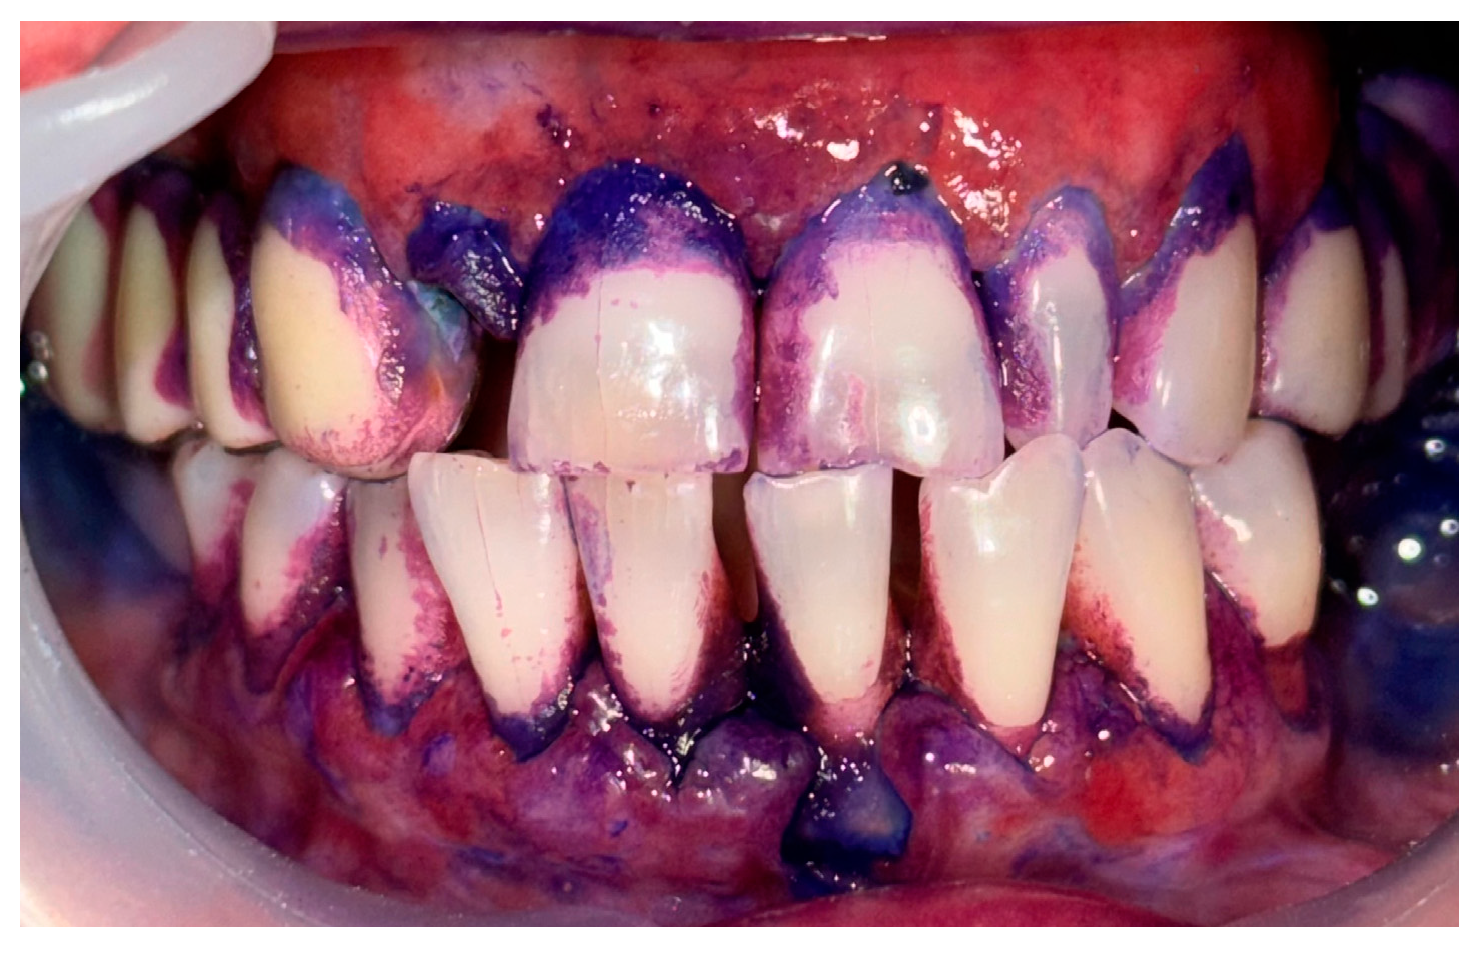

2.1. Clinical Case 1—Mucous Membrane Pemphigoid (MMP)

2.2. Clinical Case 2—Pemphigus Vulgaris (PV)

2.3. Clinical Case 3—Oral Lichen Planus (OLP)